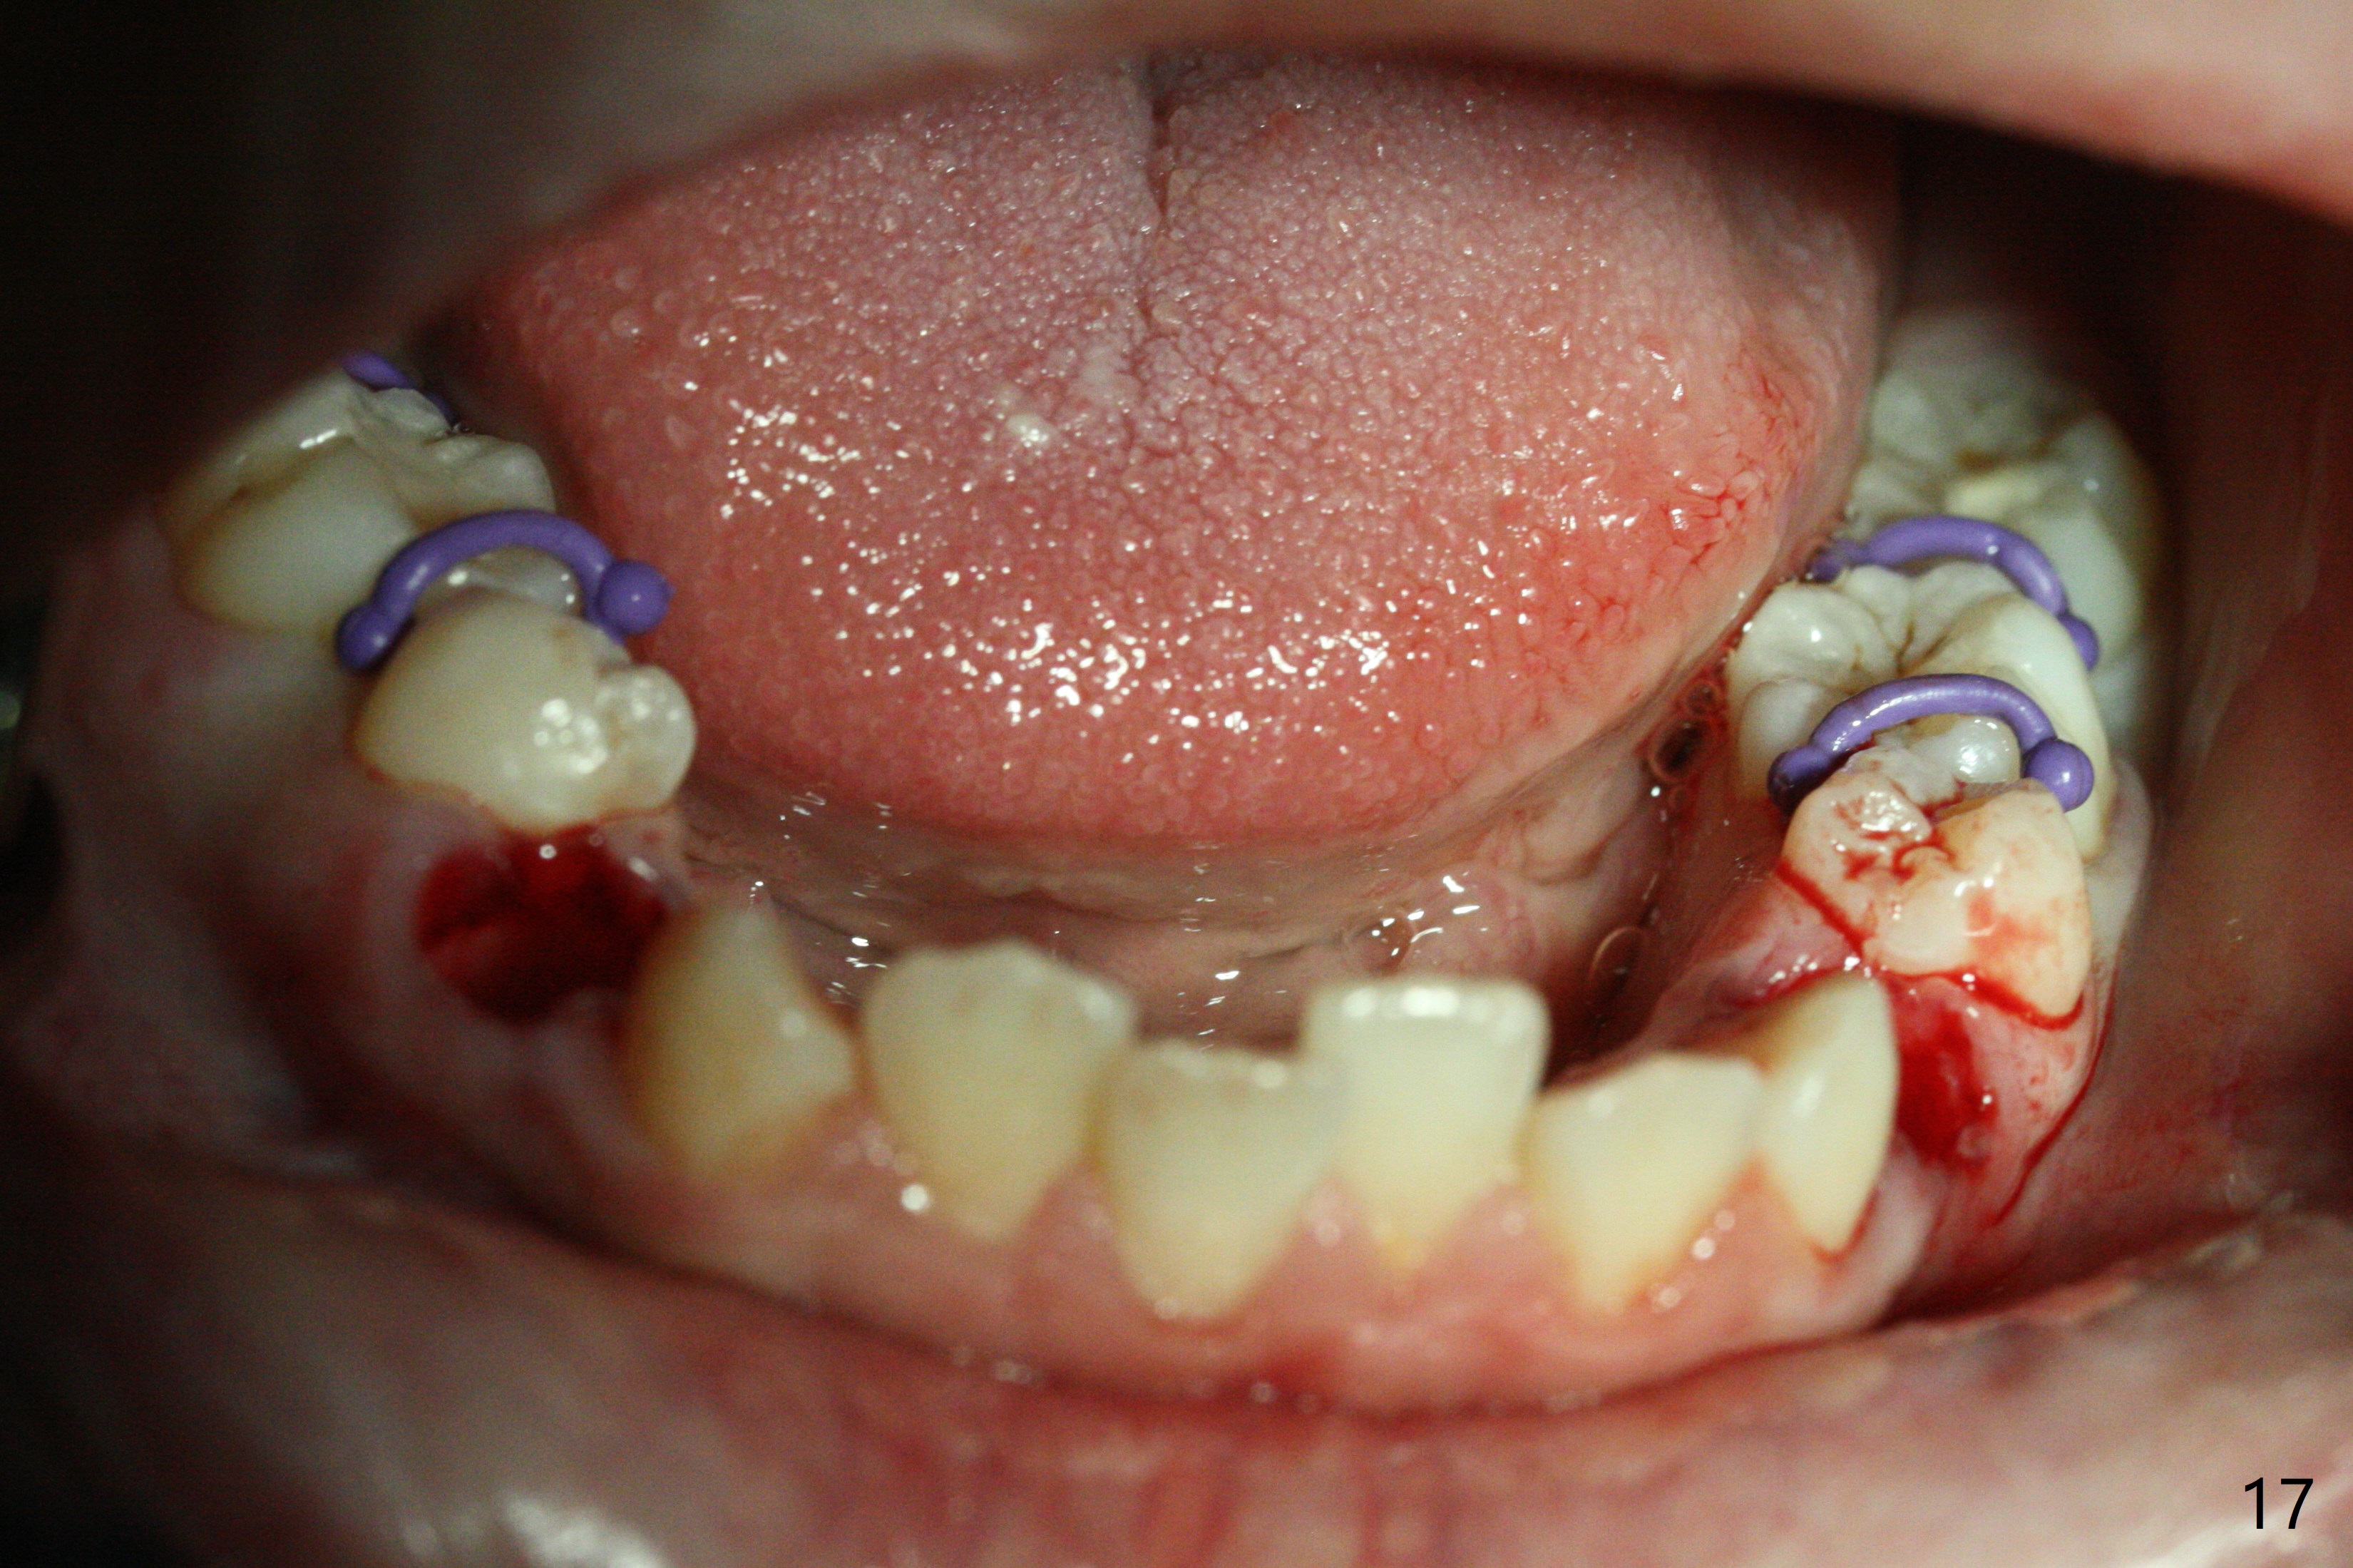

A 14-year-old woman has convex facial profile (Fig.1-4) with the upper midline shifted to the left (Fig.2). Since the roots of the 1st bicuspids are short (Fig.5), extraction should be easy. U3 will be retracted distal early with intention to correct the upper midline. With Class I occlusion at the canines and the 1st molars and good initial interdigitation (Fig.6-11), orthodontic treatment should be rewarding. Because of severe crowding (tight contact, Fig.12,13), place separators after extraction and place bands and brackets a few days later. Cephalometric analysis (Fig.14) shows that SNB is greater than SNA (82.4 vs. 81.8 degree); after extraction, retract the lower anterior teeth prior to the upper ones. It is easy to place separators after extraction (Fig.16,17).